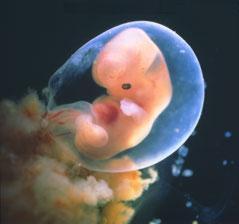

29.4. druhá KO u dr 7+3, 12,3mm a srdíčko bije

23.5. pro průkazku + odběr krve + utz 11+0 mimisek 4,2cm